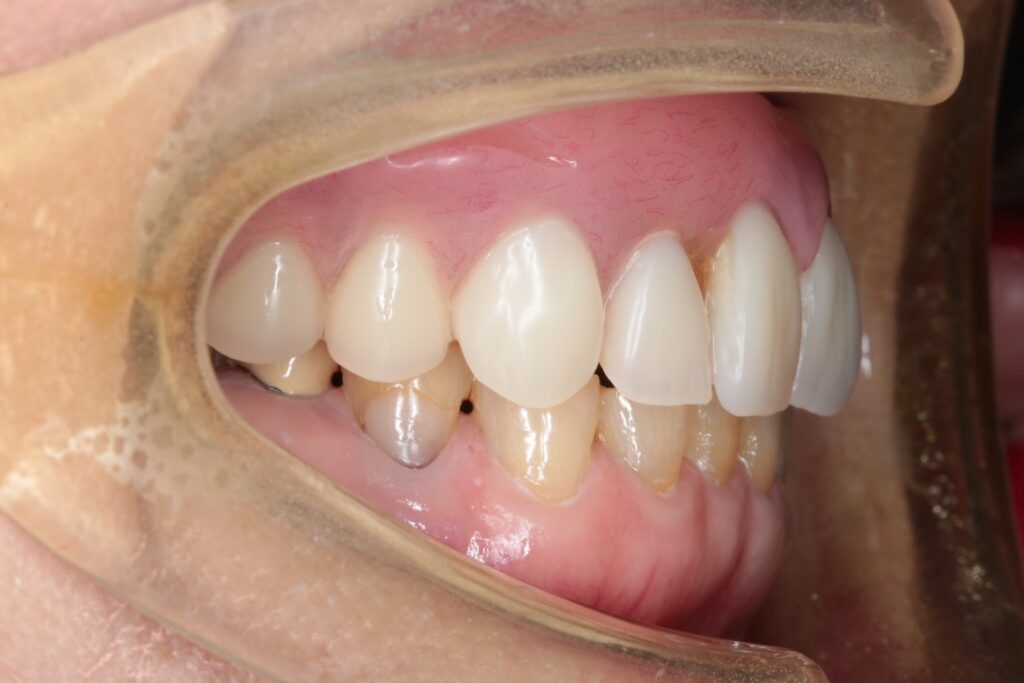

▼下顎

過去にブリッジ治療が行われていた部分を撤去し、インプラント治療へ変更。

骨が不足していたため、骨移植(GBR)を併用しています。

■術後の状態

治療後の写真を見ると、上下ともに大きく審美性が改善し、笑顔の印象も自然になりました。